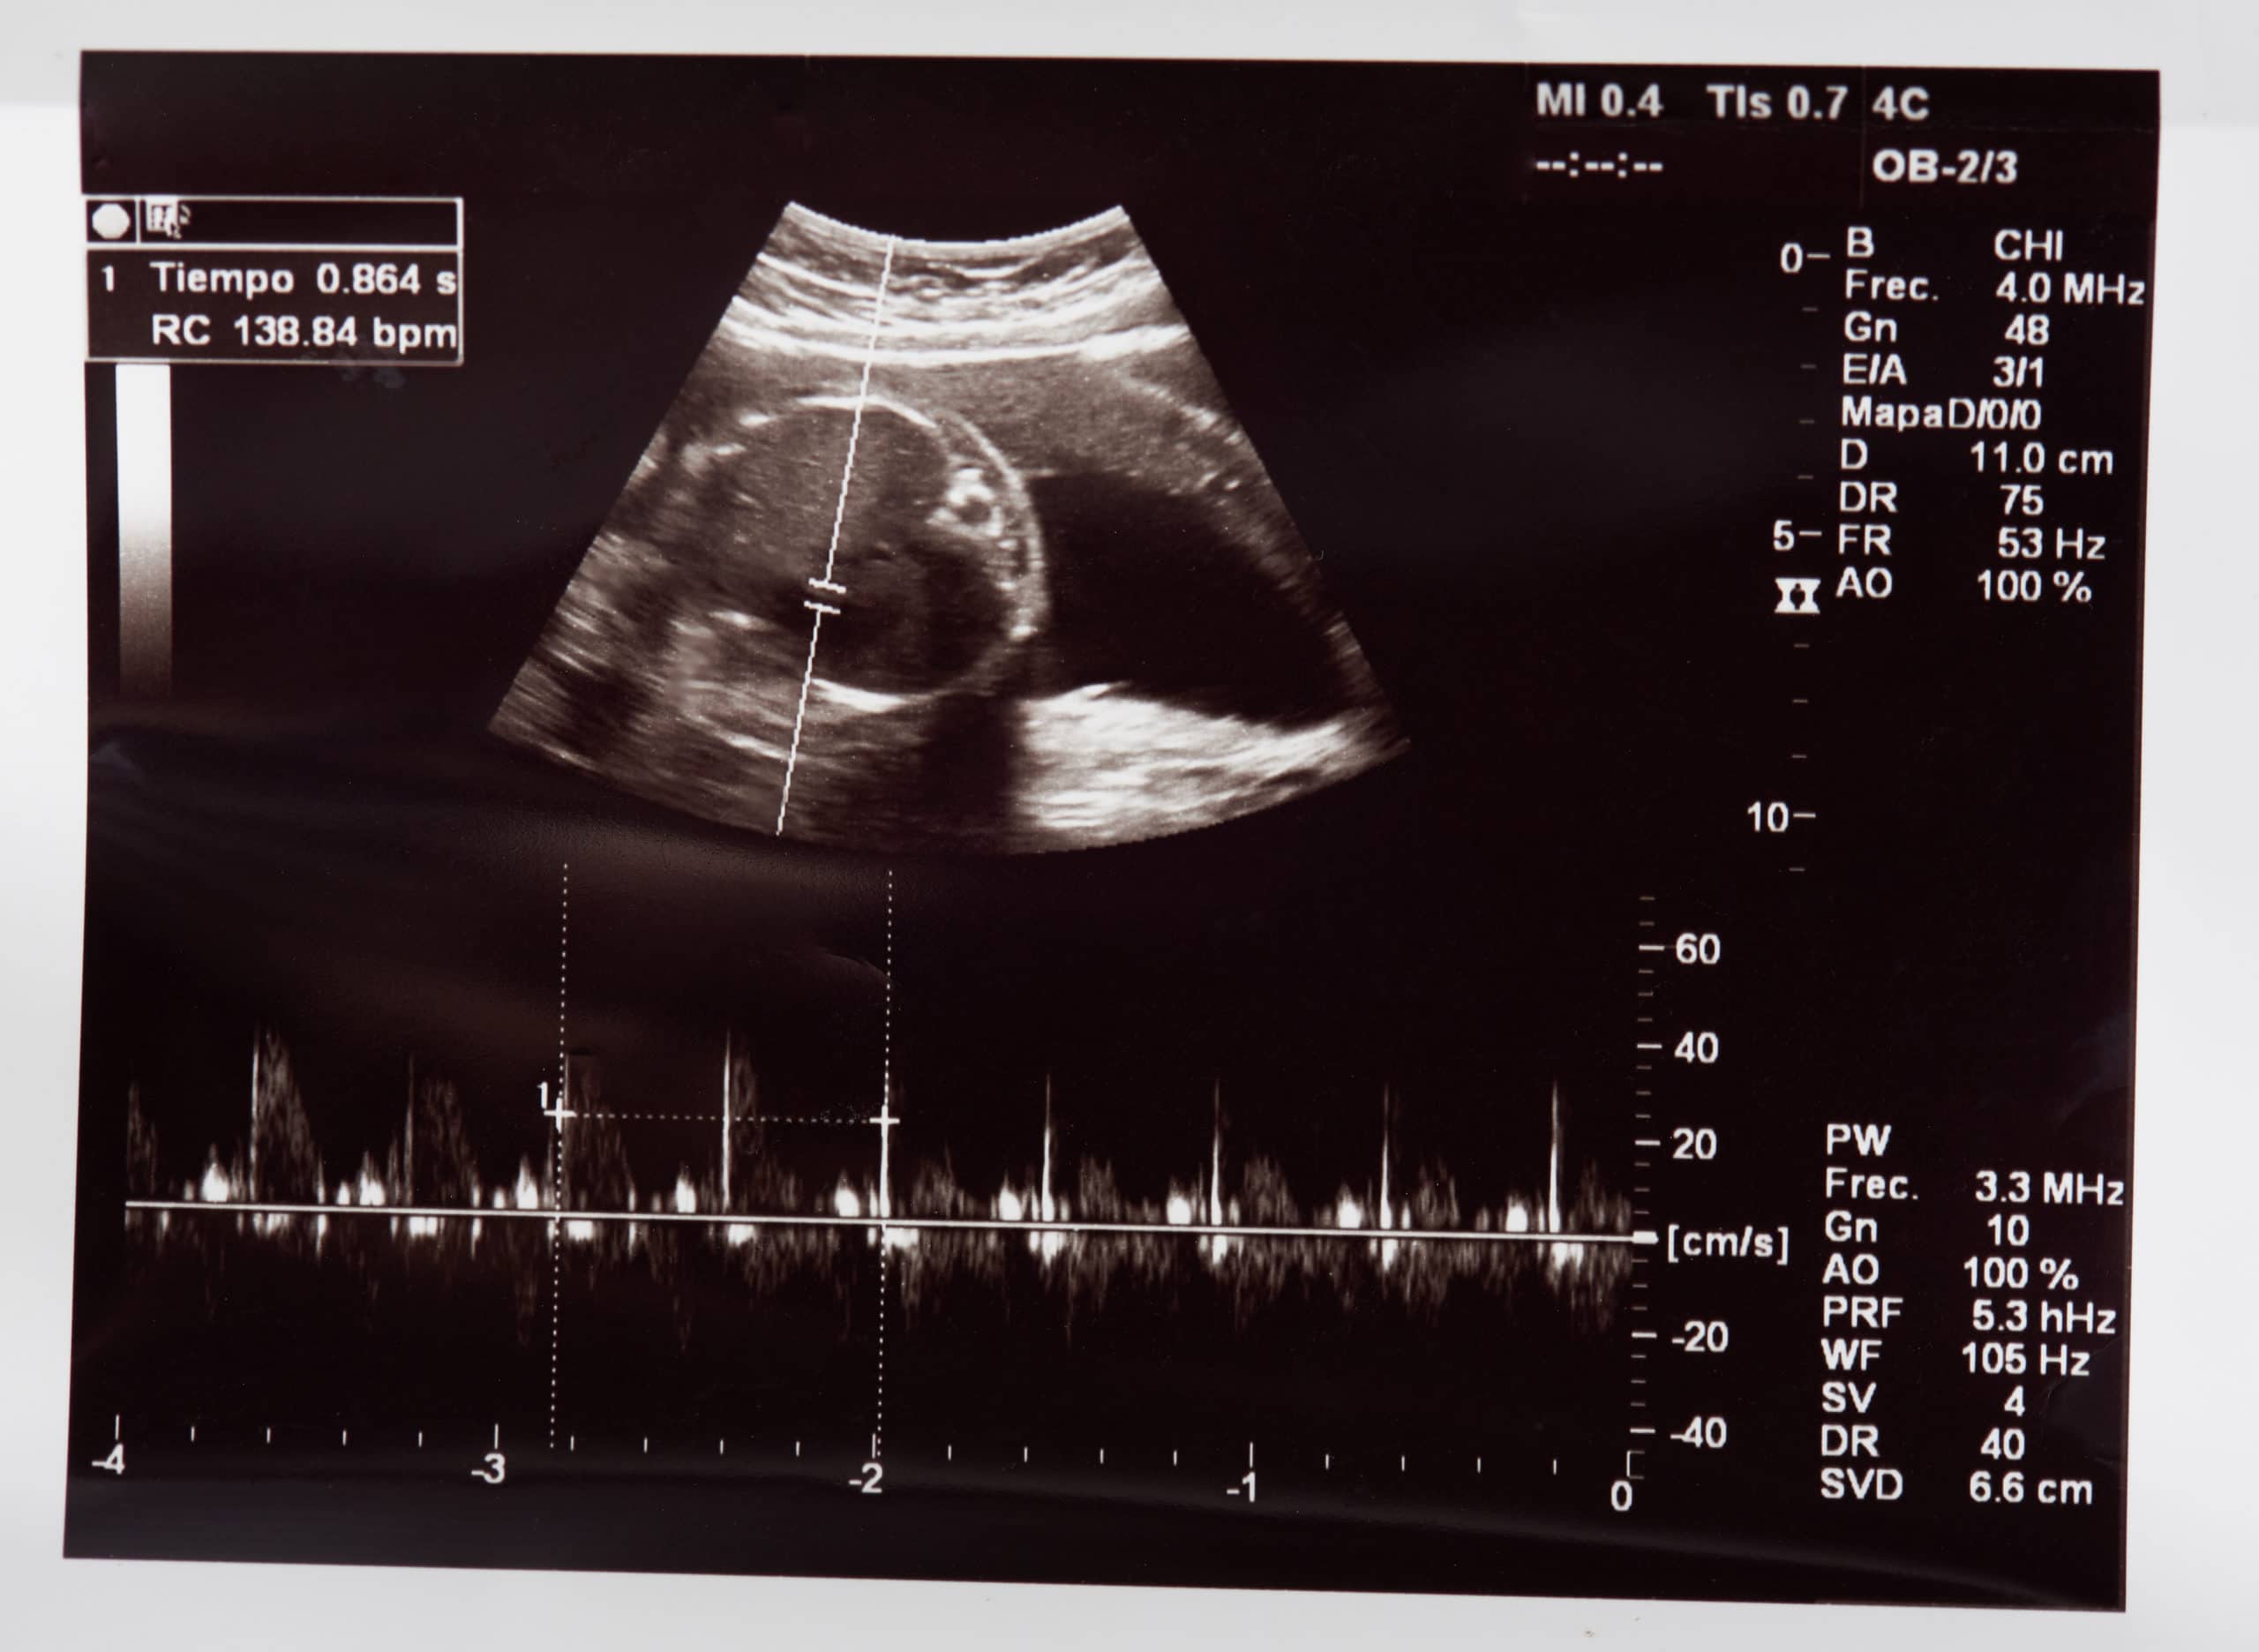

Monitor of baby's heartbeat inside womb before being born in the Baby Heart Beat In Womb fetal heart rate monitoring measures the heart rate and rhythm of your baby (fetus). when does your baby develop a heartbeat? This lets your healthcare provider see how your baby is doing. you may be able to hear your baby’s heartbeat as early as 6 weeks past gestation if you have an early ultrasound. What is fetal. Baby Heart Beat In Womb.

Baby Heart Beat In Womb . In most cases, an ultrasound can detect the beating of cardiac tissue around weeks five to six. you may be able to hear your baby’s heartbeat as early as 6 weeks past gestation if you have an early ultrasound. when does your baby develop a heartbeat? your caregiver may be able to find cardiac activity with a handheld doppler as early as 10 weeks, but the timing. A baby's heartbeat (at this point a fluttering of cells) starts as early as to 4. Very early in pregnancy, it is. fetal heart rate monitoring measures the heart rate and rhythm of your baby (fetus). What is fetal heart rate monitoring? At how many weeks of. This lets your healthcare provider see how your baby is doing. a normal heart rate for a fetus can range from 110 to 160 beats per minute (bpm).